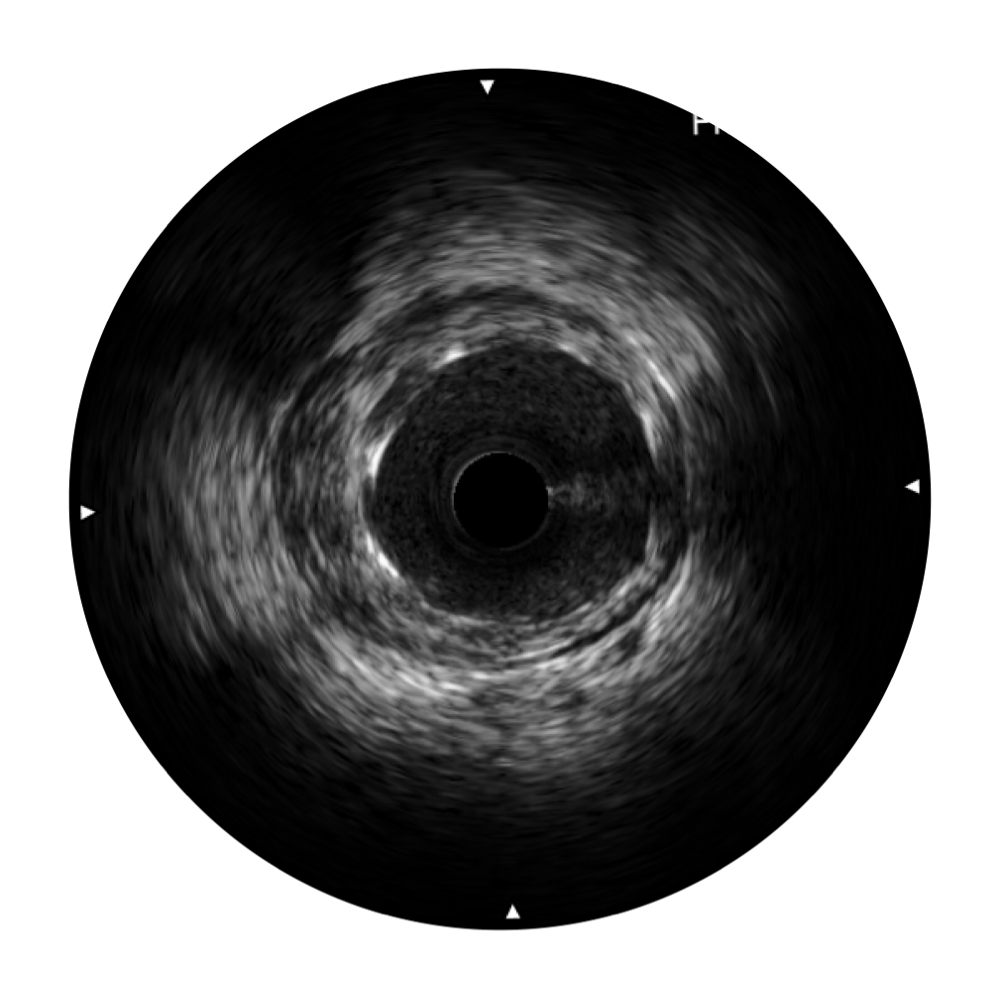

百老汇电子游戏官网宽频IVUS图像

对比传统IVUS导管成像,百老汇电子游戏官网宽频IVUS图像的近场支架梁显影更细腻,远场中膜外血管仍清晰可辨,兼顾远中近,兼顾分辨力与穿透深度